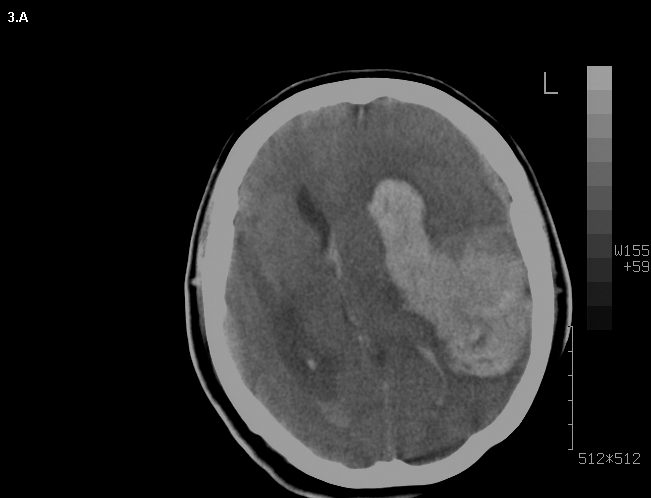

Mujer de 46 años que ingreso por cefalea súbita, hemiparesia izquierda y disartria, con tomografía axial computarizada cerebral simple que mostró hemorragia frontoparietal derecha drenada a ventrículos y arteriografía con patrón Moyamoya. Reingreso 3 meses después con deterioro del estado de consciencia y tomografía axial computarizada cerebral simple que mostró hemorragia intraparenquimatosa temporoparietal izquierda con extensión intraventricular y desviación de la línea media, se manejo en Unidad de Cuidados Intensivos con traqueostomía y gastrostomía, presentó neumonía y sepsis nosocomial, finalmente falleció en la Unidad de Cuidados Intensivos.